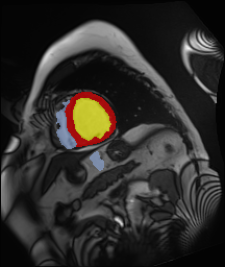

Medical data often exhibits long-tail distributions with heavy class imbalance, which naturally leads to difficulty in classifying the minority classes (i.e., boundary regions or rare objects). Recent work has significantly improved semi-supervised medical image segmentation in long-tailed scenarios by equipping them with unsupervised contrastive criteria. However, it remains unclear how well they will perform in the labeled portion of data where class distribution is also highly imbalanced. In this work, we present ACTION++, an improved contrastive learning framework with adaptive anatomical contrast for semi-supervised medical segmentation. Specifically, we propose an adaptive supervised contrastive loss, where we first compute the optimal locations of class centers uniformly distributed on the embedding space (i.e., off-line), and then perform online contrastive matching training by encouraging different class features to adaptively match these distinct and uniformly distributed class centers. Moreover, we argue that blindly adopting a constant temperature $\tau$ in the contrastive loss on long-tailed medical data is not optimal, and propose to use a dynamic $\tau$ via a simple cosine schedule to yield better separation between majority and minority classes. Empirically, we evaluate ACTION++ on ACDC and LA benchmarks and show that it achieves state-of-the-art across two semi-supervised settings. Theoretically, we analyze the performance of adaptive anatomical contrast and confirm its superiority in label efficiency.

翻译:医学数据经常呈现长尾分布和重度类别不平衡,这自然导致在对少数类别(即边界区域或罕见目标)进行分类时出现困难。最近的研究在长尾情况下通过装备医学影像的无监督对比标准,明显改进了半监督医学图像分割。然而,在标记的数据部分中,类别分布也极为不平衡,因此它们的表现如何仍不清楚。在本研究中,我们介绍一种采用自适应解剖对比度改进的对半监督医学分割行动的框架(ACTION++)。具体来说,我们提出了一种自适应监督对比损失,它首先在嵌入空间上计算出不同类别的优化位置(即离线),然后通过鼓励不同类别之间的特征与这些不同和均匀分布的类别中心相适应的在线对比匹配训练来进行自适应匹配。此外,我们认为,在长尾医疗数据中盲目采用常温度$\tau$不是最优的,因此通过一个简单的余弦计划来使用动态$\tau$来产生更好的多数类别和少数类别之间的分离。在实证方面,我们在ACDC和LA基准测试中评估ACTION++,并展示了其在两种半监督设置下的最新成果。从理论上讲,我们分析了自适应解剖对比度的性能,并证实了它在标签效率上的优越性。